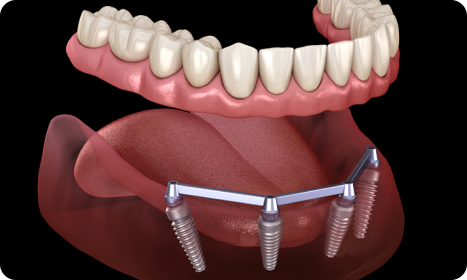

What are Full Mouth Dental Implants?

Full Mouth Dental Implants are beneficial for those who have lost a majority if not all of their teeth or have severe dental issues. The process consists of multiple implants placed in the jawbone and on each of the implants, a full set of prosthetic teeth is affixed. It provides unmatched functional strength, natural appearance, and great reliability for years—allowing patients to eat, talk, and smile confidently as if they had natural teeth.

Full Mouth Dental Implants